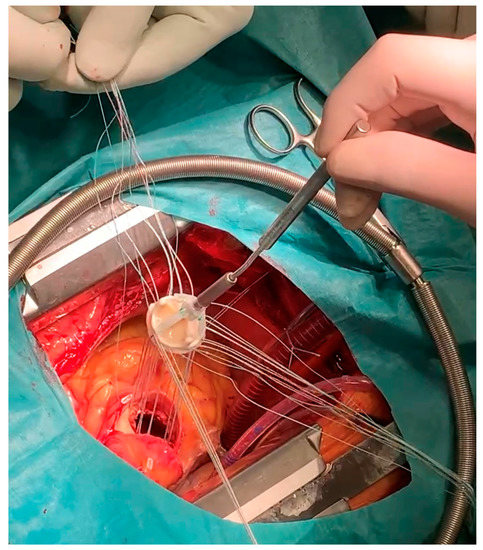

2. Case Report